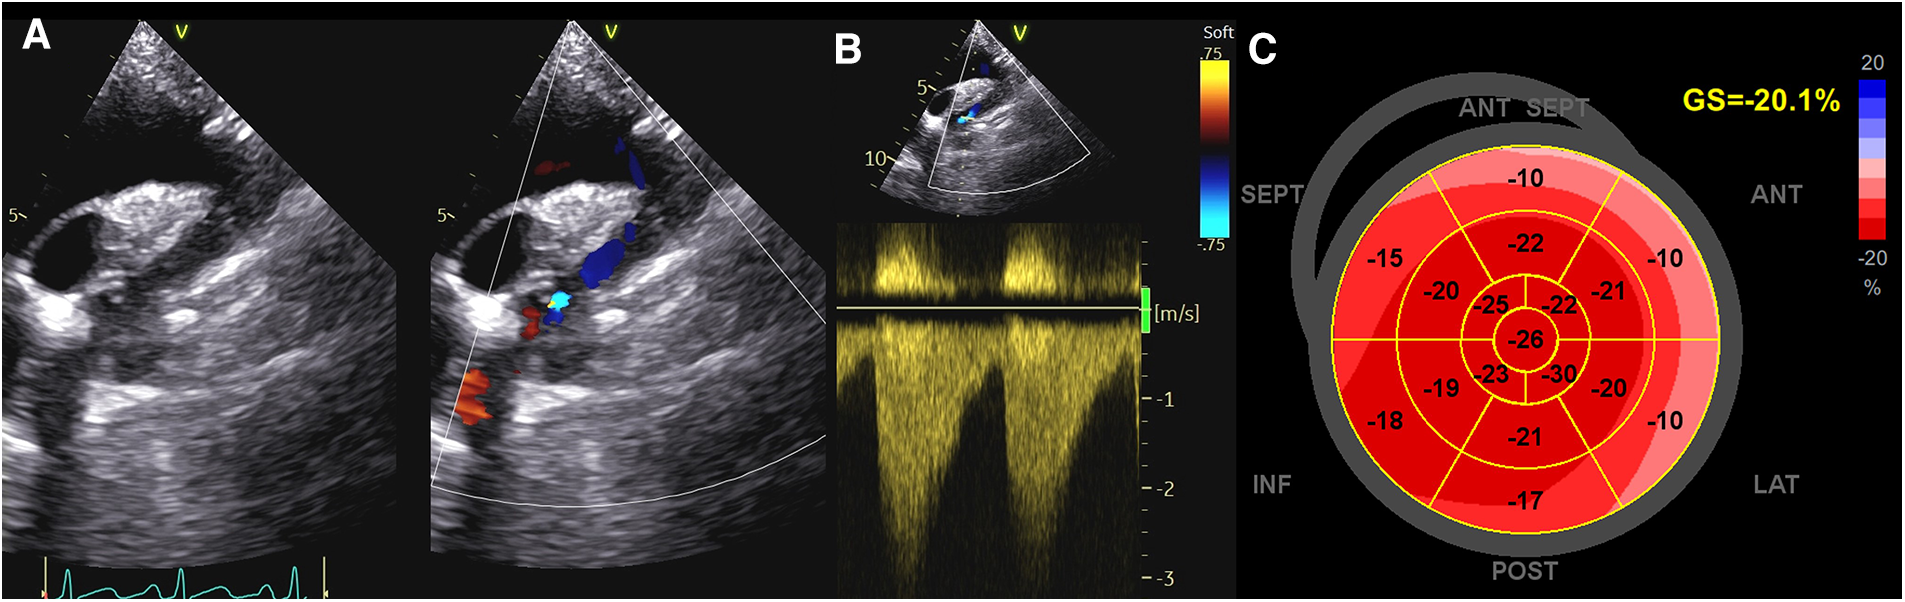

In addition, a reduction of longitudinal strain values of basal septal segment (≤−16.6%) and of LV twist were found to be the best predictors of masked hypertension in adolescents with repaired CoA. The impairment of basal segment function, which is impaired also in hypertensive heart disease, could probably be explained by the increased regional stress on the basal subendocardial longitudinal fibers at that level (22) (Figure 1).

Figure 1

Evaluation of systolic function in a patient with coarctation of the aorta. (A,B) CoA as assessed by Color and CW Doppler; (C) GLS values in the same patient. As noticed, strain values are reduced in basal segments, which are impaired also in hypertensive patients. CoA, coarctation of the aorta; CW, continuous Doppler; GLS, global longitudinal strain.